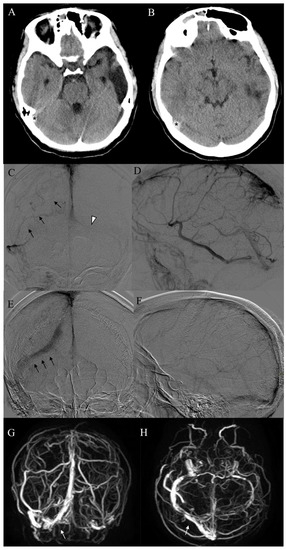

| 1 | F, 72 | Headache, nausea, aphasia, rt hemisyndrome | No identifiable risk | SSS, SS, SrS, TS, VG | SAH | 7 h | Rescue | Combined Aspiration plus Stentriever |

| 2 | F, 84 | Headache, aphasia, rt hemisyndrome | No identifiable risk | TS, ICV, VG, TS, SS | No | 5 h | Primary | Combined Aspiration plus Stentriever |

| 3 | M, 52 | Headache, nausea, dizziness | Antiphospholipid antibodies + | TS | IPH, SAH | 6 h | Primary | Aspiration |

| 4 | F, 51 | Headache, rt hemisyndrome, seizures | Contraceptive pill, MTHFR mutation | SSS | IPH, SAH | 2 h | Primary | Aspiration |

| 5 | F, 40 | Headache, aphasia, seizures | Antithrombine III and Protein S deficiency, contraceptive pill | TS, SS, JV | IPH | 7 h | Rescue | Aspiration |

| 6 | F, 44 | Headache, lt hemisyndrome, seizures | No identifiable risk | SSS | SAH | 1 h | Rescue | Aspiration |

| 7 | M, 41 | Headache, nausea, photophobia, lt sup. arm deficit | ANA+ | SSS | IPH | 2 h | Primary | Combined Aspiration plus Stentriever |

| 8 | F, 44 | Headache, aphasia | Contraceptive pill, activate protein C resistance | TS, SS | SAH | 4 h | Primary | Aspiration |

| 9 | F, 76 | Headache, seizures, loss of consciousness | No identifiable risk | SSS, SrS, TS (both), SS | No | 5 h | Primary | Aspiration |

| 10 | F, 33 | Headache, nausea, lt hemisyndrome | Pregnancy | SSS, SrS, TS (both), SS (both) | No | 2 h | Primary | Combined Aspiration plus Stentriever |

| 11 | F, 49 | Headache, vomiting, dizziness, aphasia, rt hemisyndrome | Recent pulmonary embolism | SSS, TS (both), SrS, | IPH, SAH | 2 h | Primary | Combined Aspiration plus Stentriever |

| 12 | F, 49 | Headache, nausea, dizziness, lt sup. arm deficit | Contraceptive pill, C677T and A1298C MTHFR mutation | Panthrombosis | No | 2 h | Primary | Aspiration |

| 13 | F, 45 | Headache | No identifiable risk | TS, SS | SAH | 6 h | Primary | Aspiration |

| 14 | F, 44 | Headache, nausea, aphasia, rt hemisyndrome | Contraceptive pill | TS | IPH | 3 h | Primary | Combined Aspiration plus Stentriever |

| 15 | M, 83 | Aphasia, rt hemisyndrome | Progestogen therapy | SSS, TS, SS, JV | IPH | 24 h | Rescue | Combined Aspiration plus Stentriever |

| 16 | M, 49 | GCS 9 | Neurosurgery 9 days prior | SSS, TS | No | 5 days | Rescue | Aspiration |

| 17 | F, 16 | Headache, nausea | Previous contralateral CVT, Prothrombin gene mutation | SSS, TS, SS | No | 2 h | Primary | Aspiration |

| 18 | F, 40 | Headache, nausea, rt hemiparesis | Prothrombin gene mutation (A20210G homozygosis) | SSS, SrS, TS (both), SS | IPH | 48 h | Rescue | Aspiration |

| 19 | F, 27 | Headache, nausea, dizziness, lt hemisyndrome | Contraceptive pill | SSS, rt parietal vein | IPH | 48 h | Rescue | Combined Aspiration plus Stentriever |

| 20 | F, 27 | Headache, nausea, rt hemisyndrome | Thalassemia | SSS, lt temporal vein | IPH | 48 h | Rescue | Combined Aspiration plus Stentriever |

| 21 | M, 19 | Headache, nausea, vomiting, dizziness | Active protein C resistance, MTHFR mutation | TS, SS | IPH, SAH | 3 h | Primary | Aspiration |